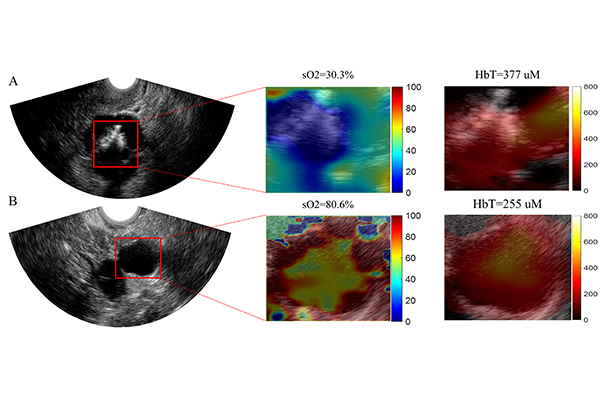

“Existing modalities are mainly based on the size and shape of the ovarian lesions which do not provide an accurate diagnosis for earlier ovarian cancer and for risk assessment of large adnexal/ovarian lesions,” said Zhu, also a professor of radiology at the School of Medicine. “Photoacoustic imaging adds more functional information about vascular contrast from hemoglobin concentration and blood oxygen saturation.”

Yun Zou, a doctoral student in Zhu’s lab, developed a new machine learning fusion model by combining an ultrasound neural network with a photoacoustic tomography neural network to perform ovarian lesion diagnosis. Cancerous lesions of the ovaries can present in several different morphologies from ultrasound: some are solid, and others have papillary projects inside cystic lesions, making them more difficult to diagnose. To improve overall diagnosis of ultrasound, they added the total hemoglobin concentration and blood oxygenation saturation from photoacoustic imaging, both of which are biomarkers for cancerous ovarian tissue. The model was tested on 655 regions of interest in 35 patients with ovarian lesions.

“Our results showed that the ultrasound-enhanced photoacoustic imaging fusion model reconstructed the target’s total hemoglobin and blood oxygen saturation maps more accurately than other methods and provided an improved diagnosis of ovarian cancers from benign lesions,” Zou said.